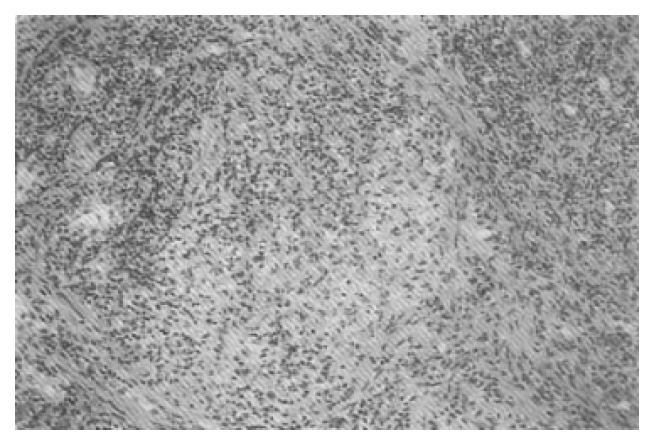

On February 5, the follow-up chest X-ray showed a much improved state but hemoglobin was decreased to 6.0g/dL; platelet 28,000/mm3. There was no clinical and laboratory evidence of hemorrhage, infection and disseminated intravascular coagulation. The peripheral blood smear showed many RBC fragments(Fig. 6); lactate dehydrogenase was increased to 902 IU/L(normal, <500IU/L) with LD1 flipped pattern; haptoglobin was reduced to below 5.8mg/L(normal, 16 to 20Omg/L); Coombs’ test and antiplatelet antibody were negative. Plasmapheresis was begun on February 10 and performed every day for 5 days.

Fig. 6.

Peripheral blood smear(Wright-Giemsa stain, ×1000) shows frequent irregular shaped erythrocyte fragments.